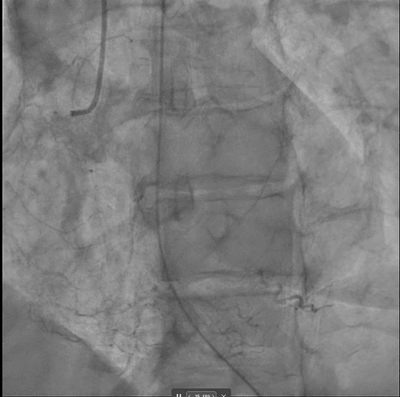

A 69-year-old woman presented with cardiac arrest and inferior STEMI on initial ECG which subsequently normalised. Despite an angiographically patent RCA and resolved ST-elevation, DeepRV flagged reduced RV function. Six hours later she deteriorated, requiring vasopressors; TTE confirmed acute RV failure. After RCA stenting, the DeepRV score normalised — illustrating real-time detection of reversible RV dysfunction beyond standard angiographic assessment.